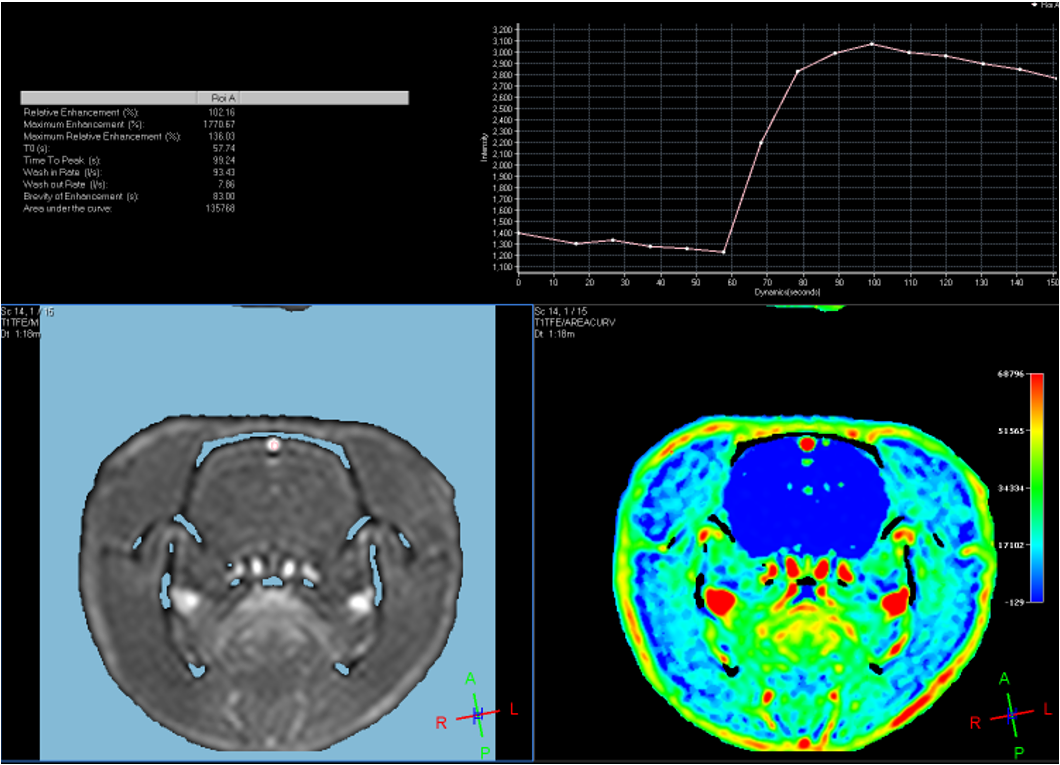

中心的研究团队包括多名医学影像领域的著名科学家和青年骨干,以医学成像和临床应用研究为核心,推动其在中国的发展,并在科技创新、产业结合方面提供多学科全球化的科研、教学和临床服务。影像中心拥有两台先进的3T全身磁共振成像系统(Philips Ingenia CX 3.0T和Siemens Prisma 3.0T),一台超高场5T全身磁共振成像系统(联影 Jupiter 5.0T),多套超声成像系统(含一台ICONEUS 脑功能超声成像系统),以及配套的成像技术、软硬件开发平台、图像数据处理工具和临床图像处理软件。中心的专业运行和技术支持团队以磁共振平台为核心,面向用户提供优秀的基础科学研究、成像技术研发和临床医学转化服务。

影像中心自成立以来,承担了科技部、国家自然科学基金委、卫生部、北京市科委等近百项国家和省部级项目,收到各种研究经费支持达5000万余元,已发表论文600余篇,发明专利60余项,国际专利10余项,培养学生130余人,获得各种奖励30余项。影像中心已成为全球重要的医学影像尤其是磁共振技术研发中心,开发出大视野高分辨血管壁多对比度成像、三维心肌定量成像、定量血流成像、定量生理成像、无变形高分辨率弥散成像等诸多原创技术,同时这些技术被广泛地应用在多项大规模临床人群队列研究当中形成了针对心脑血管、神经变性性疾病等原创性影像学解决方案。